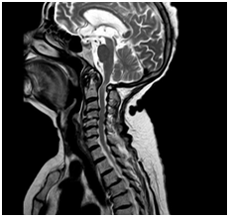

Anatómiai nyaki gerinc, láthatóvá MRI.

MRI lehetővé teszi, hogy megjelenítsék morfológiai változások: a csigolyatestek, porckorongok, gerincvelő, dura térben, az ideg gyökerek környező paravertebralis lágyrész, érrendszeri szerkezetek, amelyek a kutatási területen.

T1VI T2VI (keverjük) T2VI